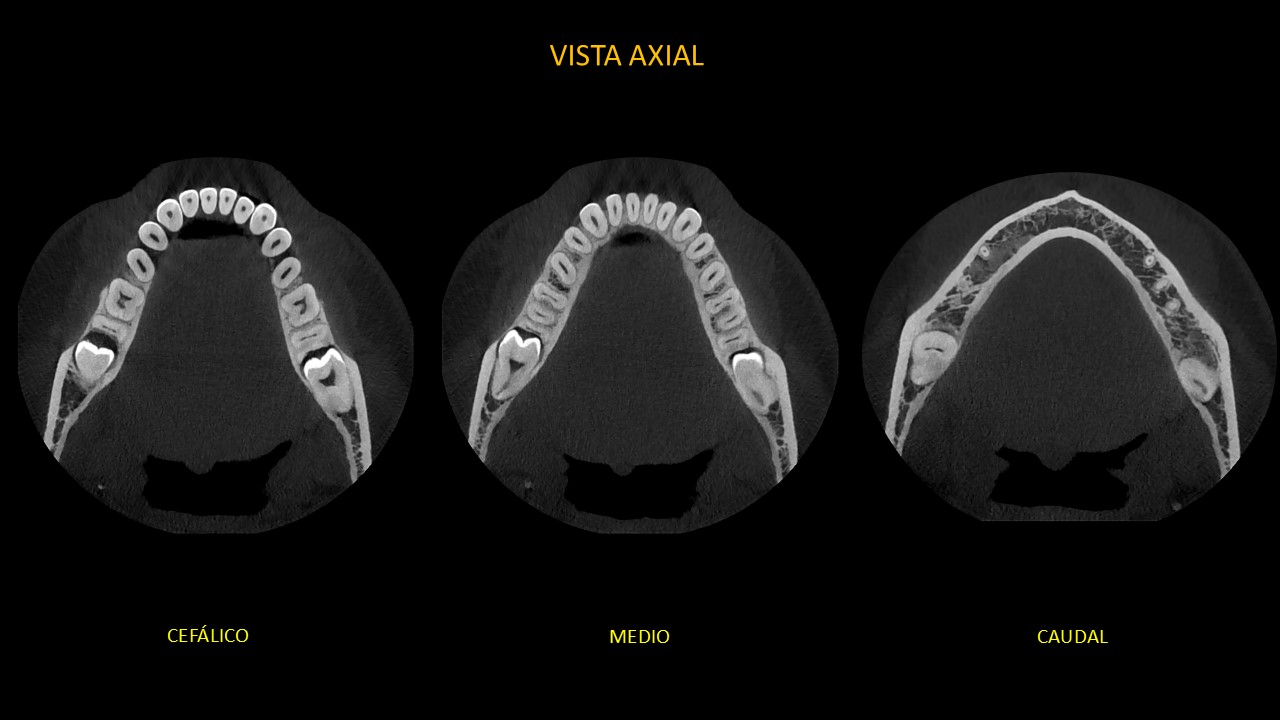

Figura 2

En cortes axiales (Figura 2), en sentido de cefálico a caudal, en la pieza 38 se observa el adelgazamiento parcial de la tabla ósea lingual y la relación de contacto de la corona con el tercio medio radicular y apical de pieza 37, ocasionando su reabsorción radicular externa. En zona de pieza 48, se observa el adelgazamiento parcial de ambas tablas óseas y la relación de contacto de la corona con el tercio cervical, medio y apical de pieza 47, ocasionando su reabsorción radicular externa.